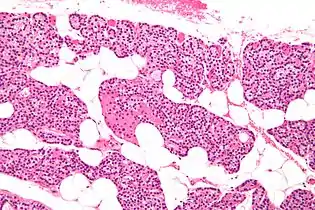

تسمى الغدد جارات الدرقية بهذا الاسم بسبب قربها من الغدة الدرقية - وتقوم بدور مختلف تمامًا عن الغدة الدرقية. يمكن تمييز الغدد جارات الدرقية بسهولة عن الغدة الدرقية حيث أنها تحتوي على خلايا مكتظة بكثافة، على النقيض من البنية الجُريبية للغدة الدرقية.[12] يوجد نوعان فريدان من الخلايا في الغدة الجار درقية:

- الخلايا الحَمِضة الدريقية، أخف في المظهر وتزداد عدديًا مع تقدم العمر،[13] ولها وظيفة غير معروفة.[14]

صورة مجهرية بتكبير عالٍ. صبغة الهيماتوكسيلين واليوزين. الخلايا ذات السيتوبلازم المصبوغ بالبرتقالي أو الوردي هي خلايا حمضة دريقية.